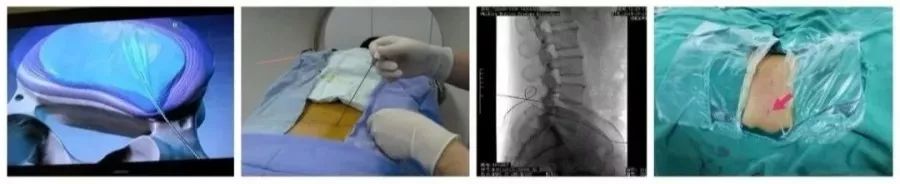

外科治疗

而对于脊椎椎管、椎间孔位置不正确,失去了代偿空间,脊髓及神经根无可逃逸的空间,仍采用保守治疗,效果欠佳,治疗是徒劳的!

而需要借助外科手术,才能解决椎间盘突出物与脊髓、神经的空间位置问题才能根本上解决问题。至于选择哪一种治疗方式,会有什么样的治疗效果,当然要咨询临床经验丰富的专科医师,获取良好治疗效果。